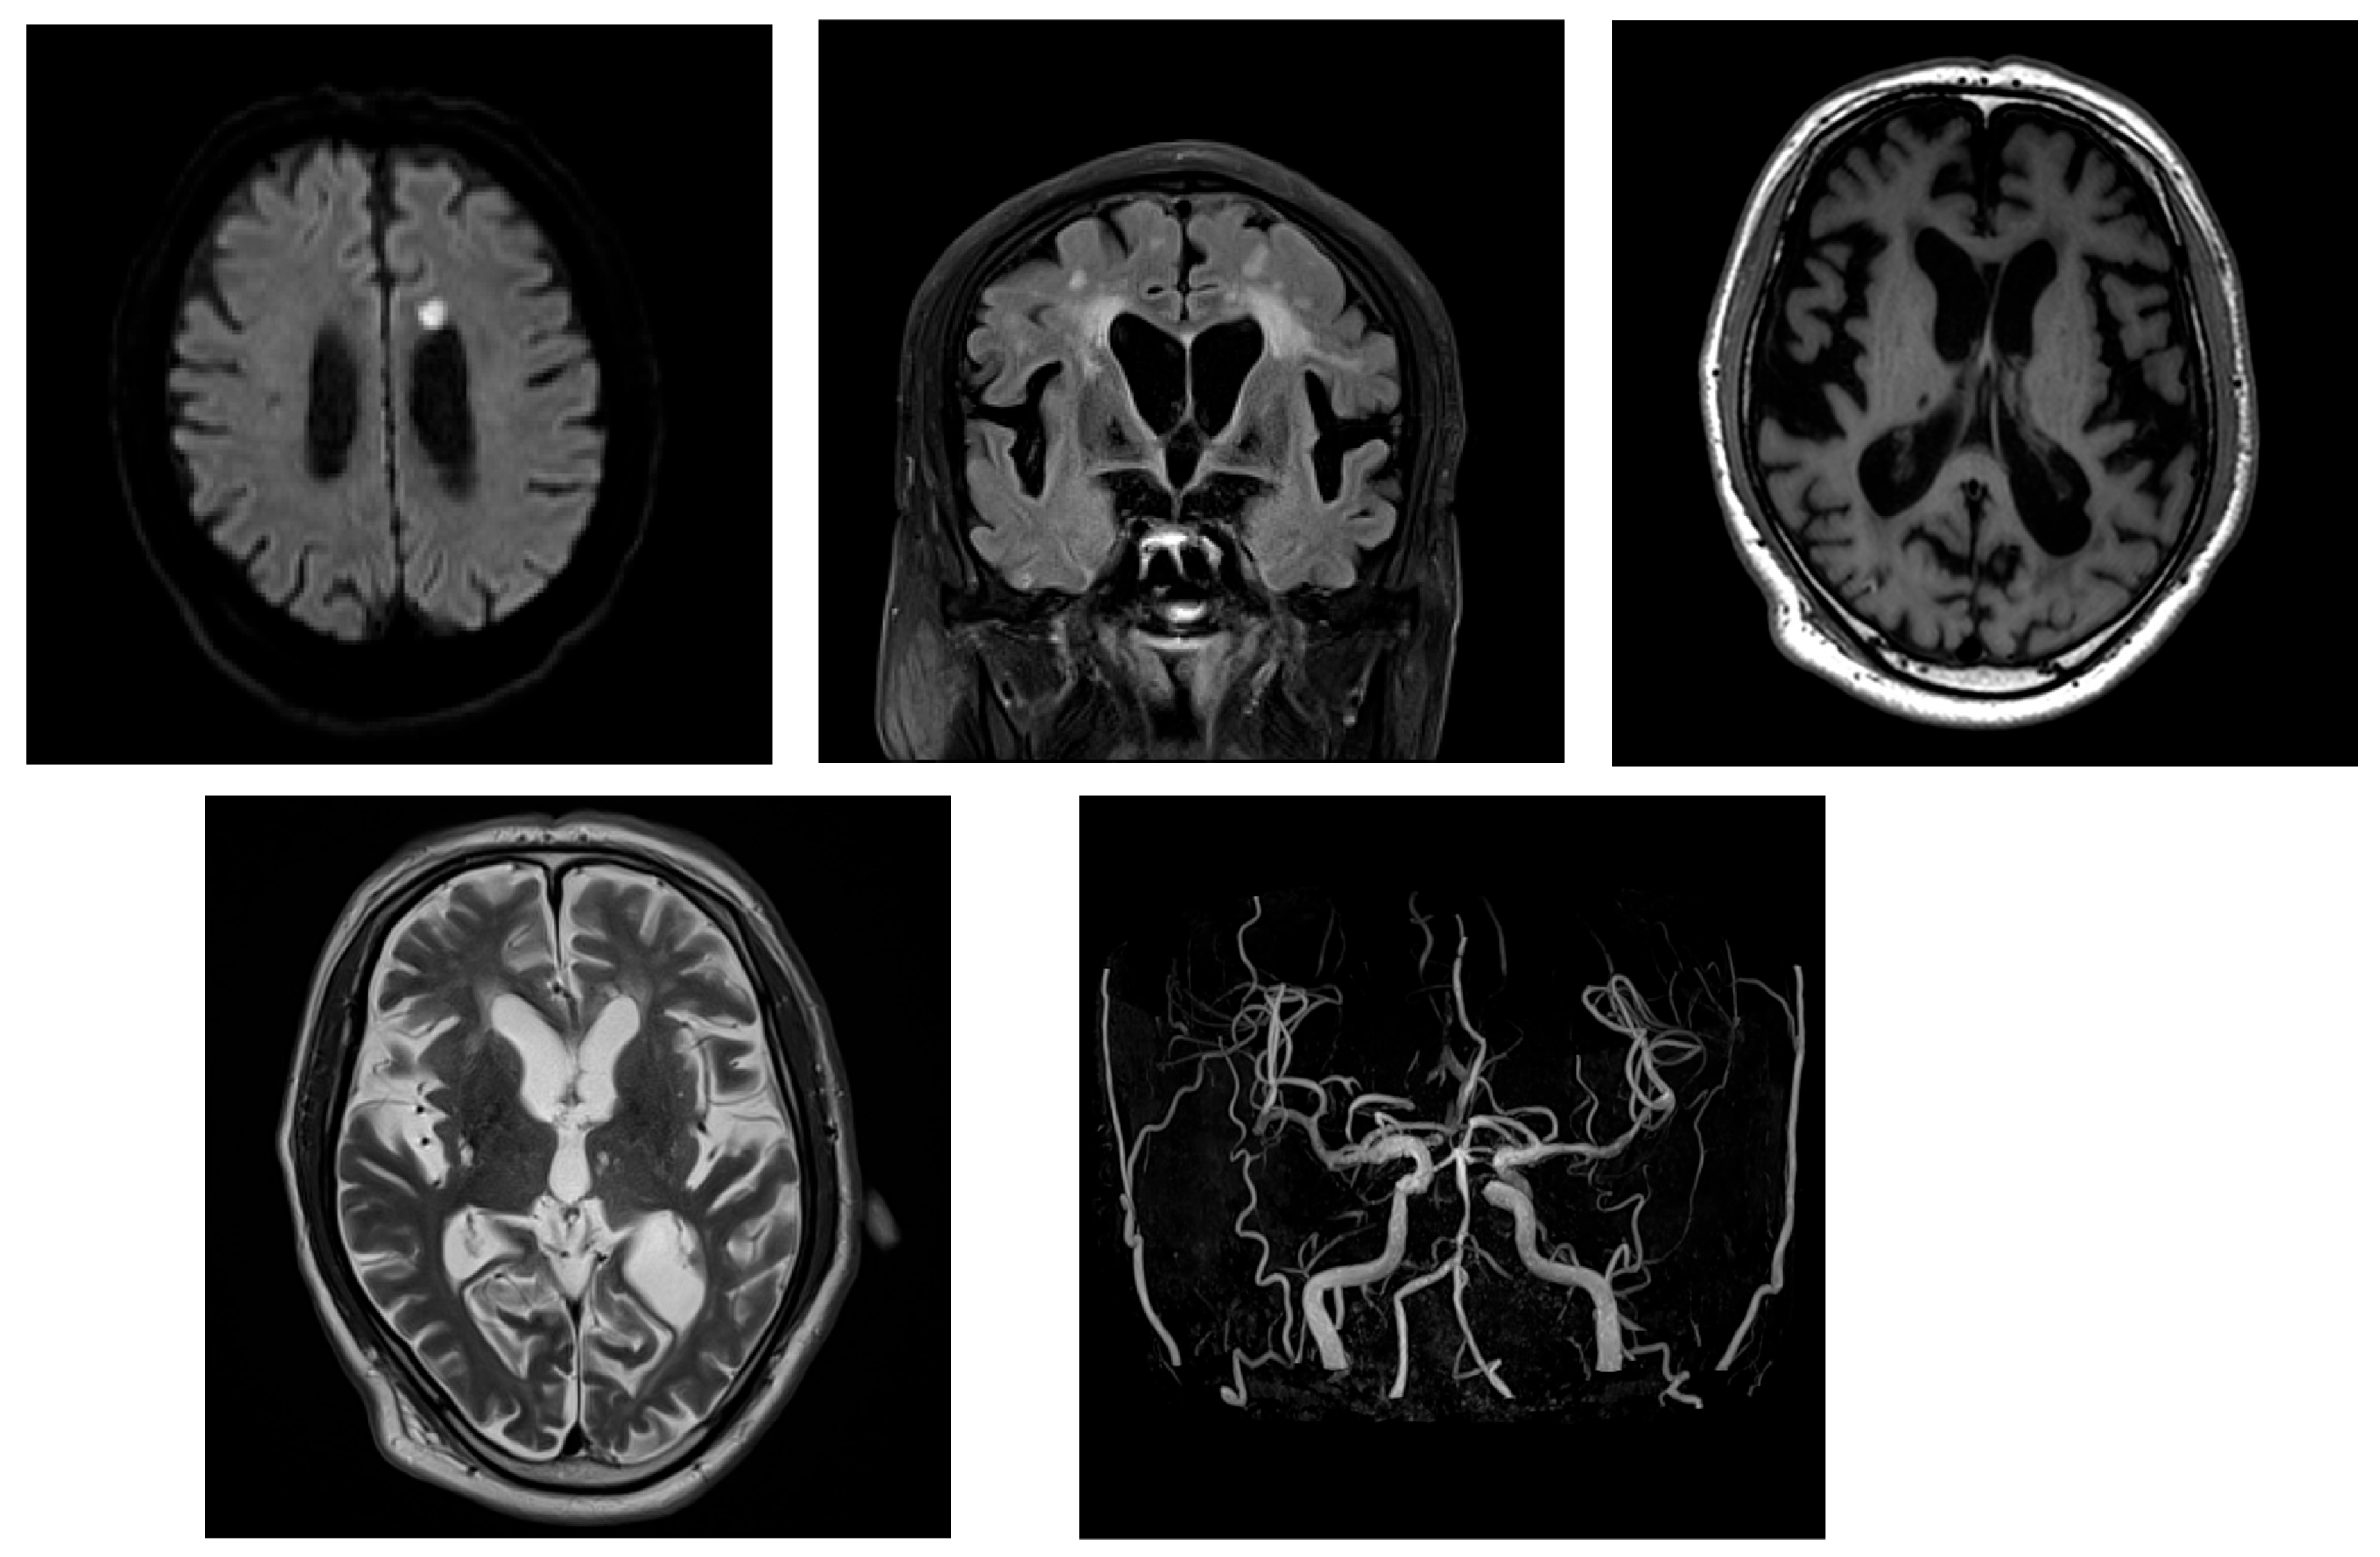

2.1. Case 1